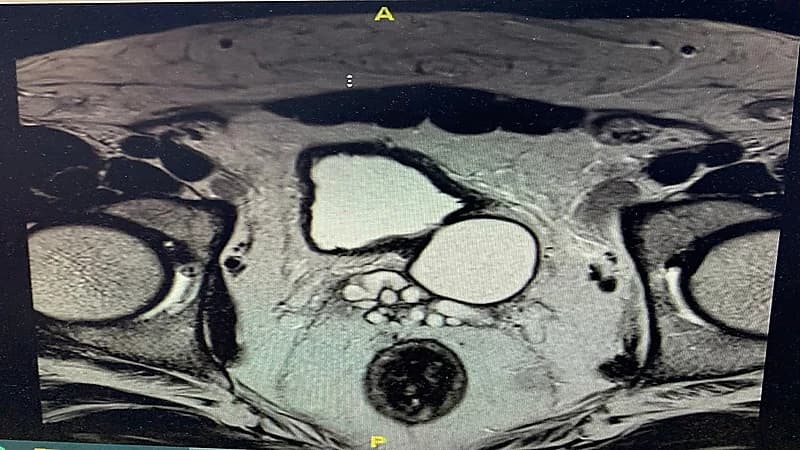

وقال التجمع الصحي في مكة المكرمة ان المريض كان يعاني من آلام مزمنة في الحوض وصعوبة في التبول وبعد الفحص وإجراء أشعة الموجات فوق الصوتية والرنين المغناطيسي قرر الفريق الطبي المعالج إجراء العملية بالمنظار الجراحي وقد تكللت بالنجاح ولله الحمد.

حيث كان المريض يعاني من " متلازمة زينر الثلاثية " وهي غياب الكلية على ناحية من الجسم مع تكيس الحويصلة المنوية خلف المثانة البولية وانسداد قناة القذف على نفس الناحية ورغم صعوبة التشخيص في هذه الحالات بسبب ندرتها وأعراضها غير المحددة مثل الآلام الحوض وعسر التبول المستمر .